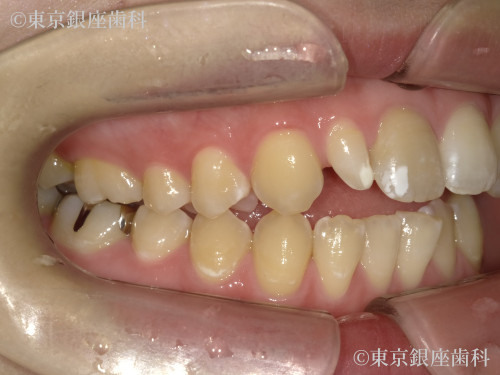

Before

20代 女性

疾患 矯正

施術内容 矯正

治療期間 1年1ヶ月 費用 90万円(税込)

インビザライン:コンプリヘンシブパッケージ